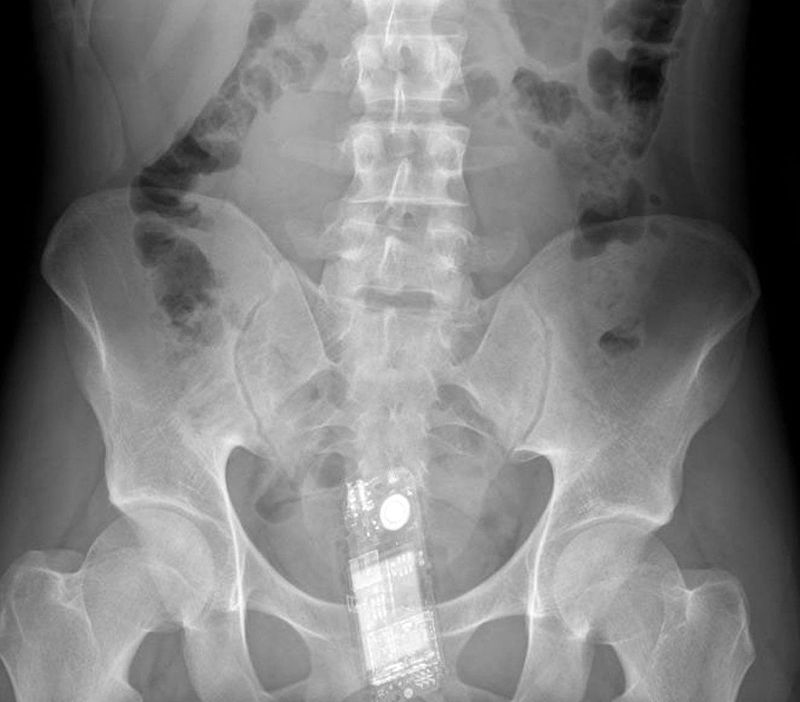

Прибывший в колонию осужденный пытался пронести с собой мобильный телефон, но не учел, что его проверят на рентгене

"Во время проведения рентгена у него был обнаружен телефон в естественной полости (анальное отверстие)", - сообщили в областном департаменте УИС.